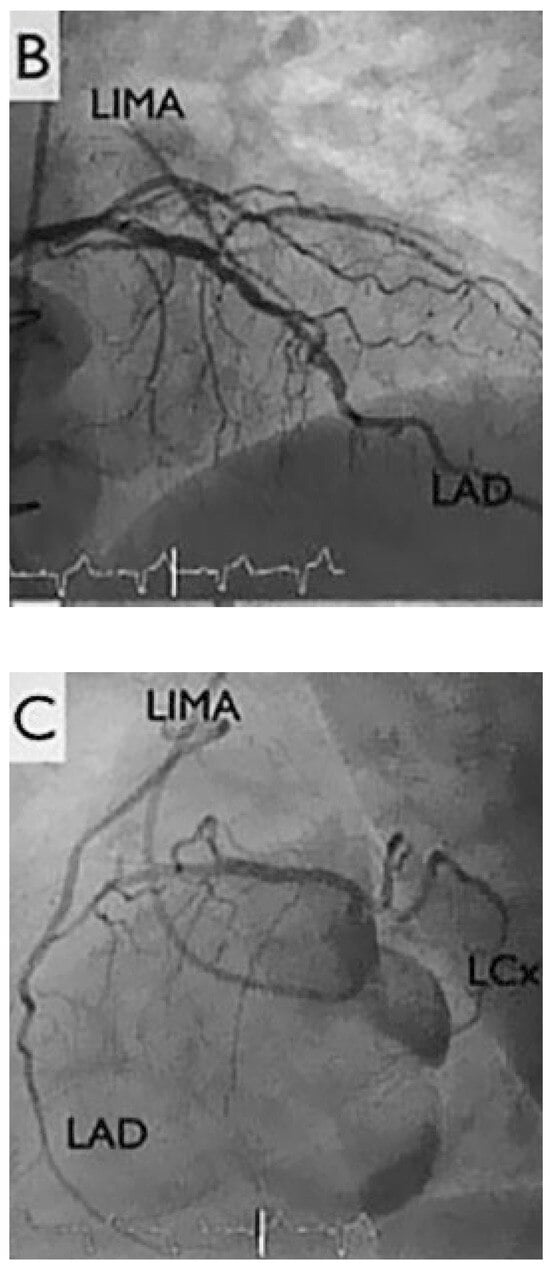

A 67-year-old diabetic patient with three-vessel coronary artery disease (Figure 1) and prior coronary artery bypass graft surgery (left internal mammary artery to left anterior descending artery, vein to marginal branch, vein to right coronary artery) suffered from refractory angina. Coronary angiography demonstrated good results after surgical revascularisation, but also a diffuse infiltration of the left coronary tree. Left ventricular systolic function was normal. The patient presented refractory angina despite optimal antianginal therapy comprising beta-blockers, nitrates, ranolazine (Ranexa®) and molsidomine (Corvaton®). The patient was severely disabled, being unable to walk 200 metres without nitrates, and waking up every 2 hours because of angina and paroxysmal dyspnoea. The treadmill test showed ischaemia.

Figure 1.

Coronary angiogram. LAD: left anterior descending artery, LCx: left circumflex artery, LIMA: left internal mammary artery, MA: marginal artery, RCA: right coronary artery, ous vein graft; LVS: left ventricular tele-systolic volume; LVD: left ventricular tele-diastolic volume.